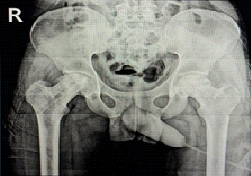

A 19-year-old male presented with bilateral hip pain and gait abnormality of 1 year’s duration. He had a prior history of steroid therapy for tuberculous meningitis. Magnetic resonance imaging (MRI) revealed bilateral AVN of the femoral heads (ARCO Stage II), and he was scheduled for bilateral core decompression with platelet-rich plasma injection (Fig. 1).

Figure 1: Post-operative X-ray.